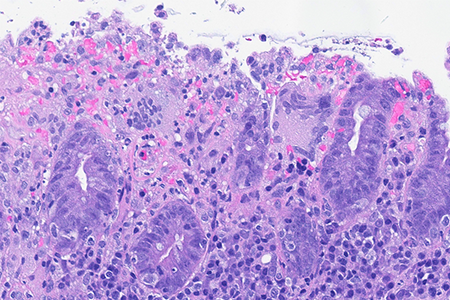

Colon biopsies in a 87 year-old female with chronic watery diarrhea.

Collagenous colitis with giant cells.

An 87-year-old woman presented with chronic, non-bloody, watery diarrhea and underwent colonoscopy, which revealed no endoscopic abnormalities. Biopsies were taken.

Histology of several colonic sites showed a thickened subepithelial collagen band (>10 μm), predominantly beneath the superficial epithelium but also surrounding the crypts (Panel A). Surface epithelial injury was also observed, with focal mucin depletion and detachment of superficial epithelial cells (Panel B). Lamina propria showed increased cellularity, with lymphocytic and plasmocytic infiltration, along with numerous giant cells (Panel C). There was no crypt architectural distortion. The collagen deposition was highlighted by Masson’s trichrome stain (Panel D) and strongly by tenascin immunohistochemistry (Panel E).

Histological variants of both collagenous and lymphocytic colitis have been described, including collagenous colitis with giant cells. In this variant, multinucleated giant cells are abundant and scattered throughout the lamina propria, with no apparent prognostic value.